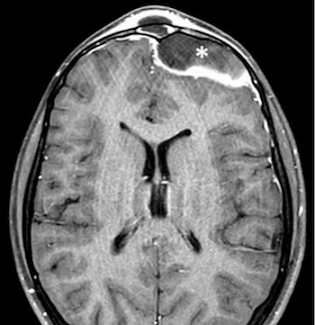

In ottava giornata di terapia, viene eseguita una RM encefalo di controllo, che mostra una riduzione della flogosi del seno frontale e, nonostante il miglioramento clinico laboratoristico e l’assenza di segni o sintomi neurologici, la comparsa di un ascesso epidurale frontale anteriore con compressione del lobo frontale (Figura 2). Viene quindi diagnosticato un tumore di Pott (PPT) e la paziente viene sottoposta a craniotomia urgente con drenaggio dell’ascesso e successiva terapia antibiotica con linezolid e cefepime.

Il PPT rappresenta una rara complicanza della sinusite frontale e consiste in un’osteomielite dell’osso frontale associata a un ascesso subperiostale. La diagnosi differenziale comprende: tumori primitivi dell’osso, istiocitosi a cellule di Langerhans e traumi. Il PPT è un fattore di rischio per complicanze intracraniche come empiema subdurale e ascessi cerebrali. Una corretta e rapida diagnosi consente un trattamento efficace e precoce, che permette di ridurre la probabilità di complicanze severe. Il trattamento comprende l’antibioticoterapia ad ampio spettro per 4-8 settimane e il drenaggio chirurgico precoce.